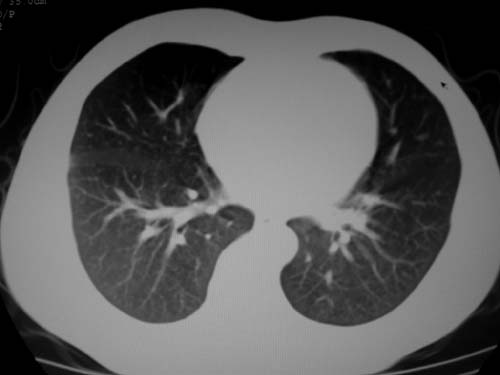

标题: CT19540: 31岁。自述结核性胸水治疗两个月后,在外院拍x线发 [打印本页]

标题: CT19540: 31岁。自述结核性胸水治疗两个月后,在外院拍x线发

右侧胸壁结节状软组织影伴相应肺叶内受侵,伴右侧胸腔积液。考虑:结核性可能大。

1、炎性包块;2、右侧少量胸膜积液。

1、炎性病变,结核可能;2、右侧少量胸膜积液。

病灶也是发生于结核球好发部位,支持结核

考虑结核性结节

多考虑包裹性胸腔识液。

右侧胸壁结节状软组织影伴相应肺叶内受侵,伴右侧胸腔积液,结合临床,首先考虑结核。

考虑结核性胸膜炎,胸膜肥厚,不除外胸膜间皮瘤可能,建议复查。

支持结核,胸膜间皮瘤不排除.

1)考虑右侧结核性胸膜结节。2)右侧胸膜增厚+包裹性胸腔积液。

结核性脓胸、肺内结核?